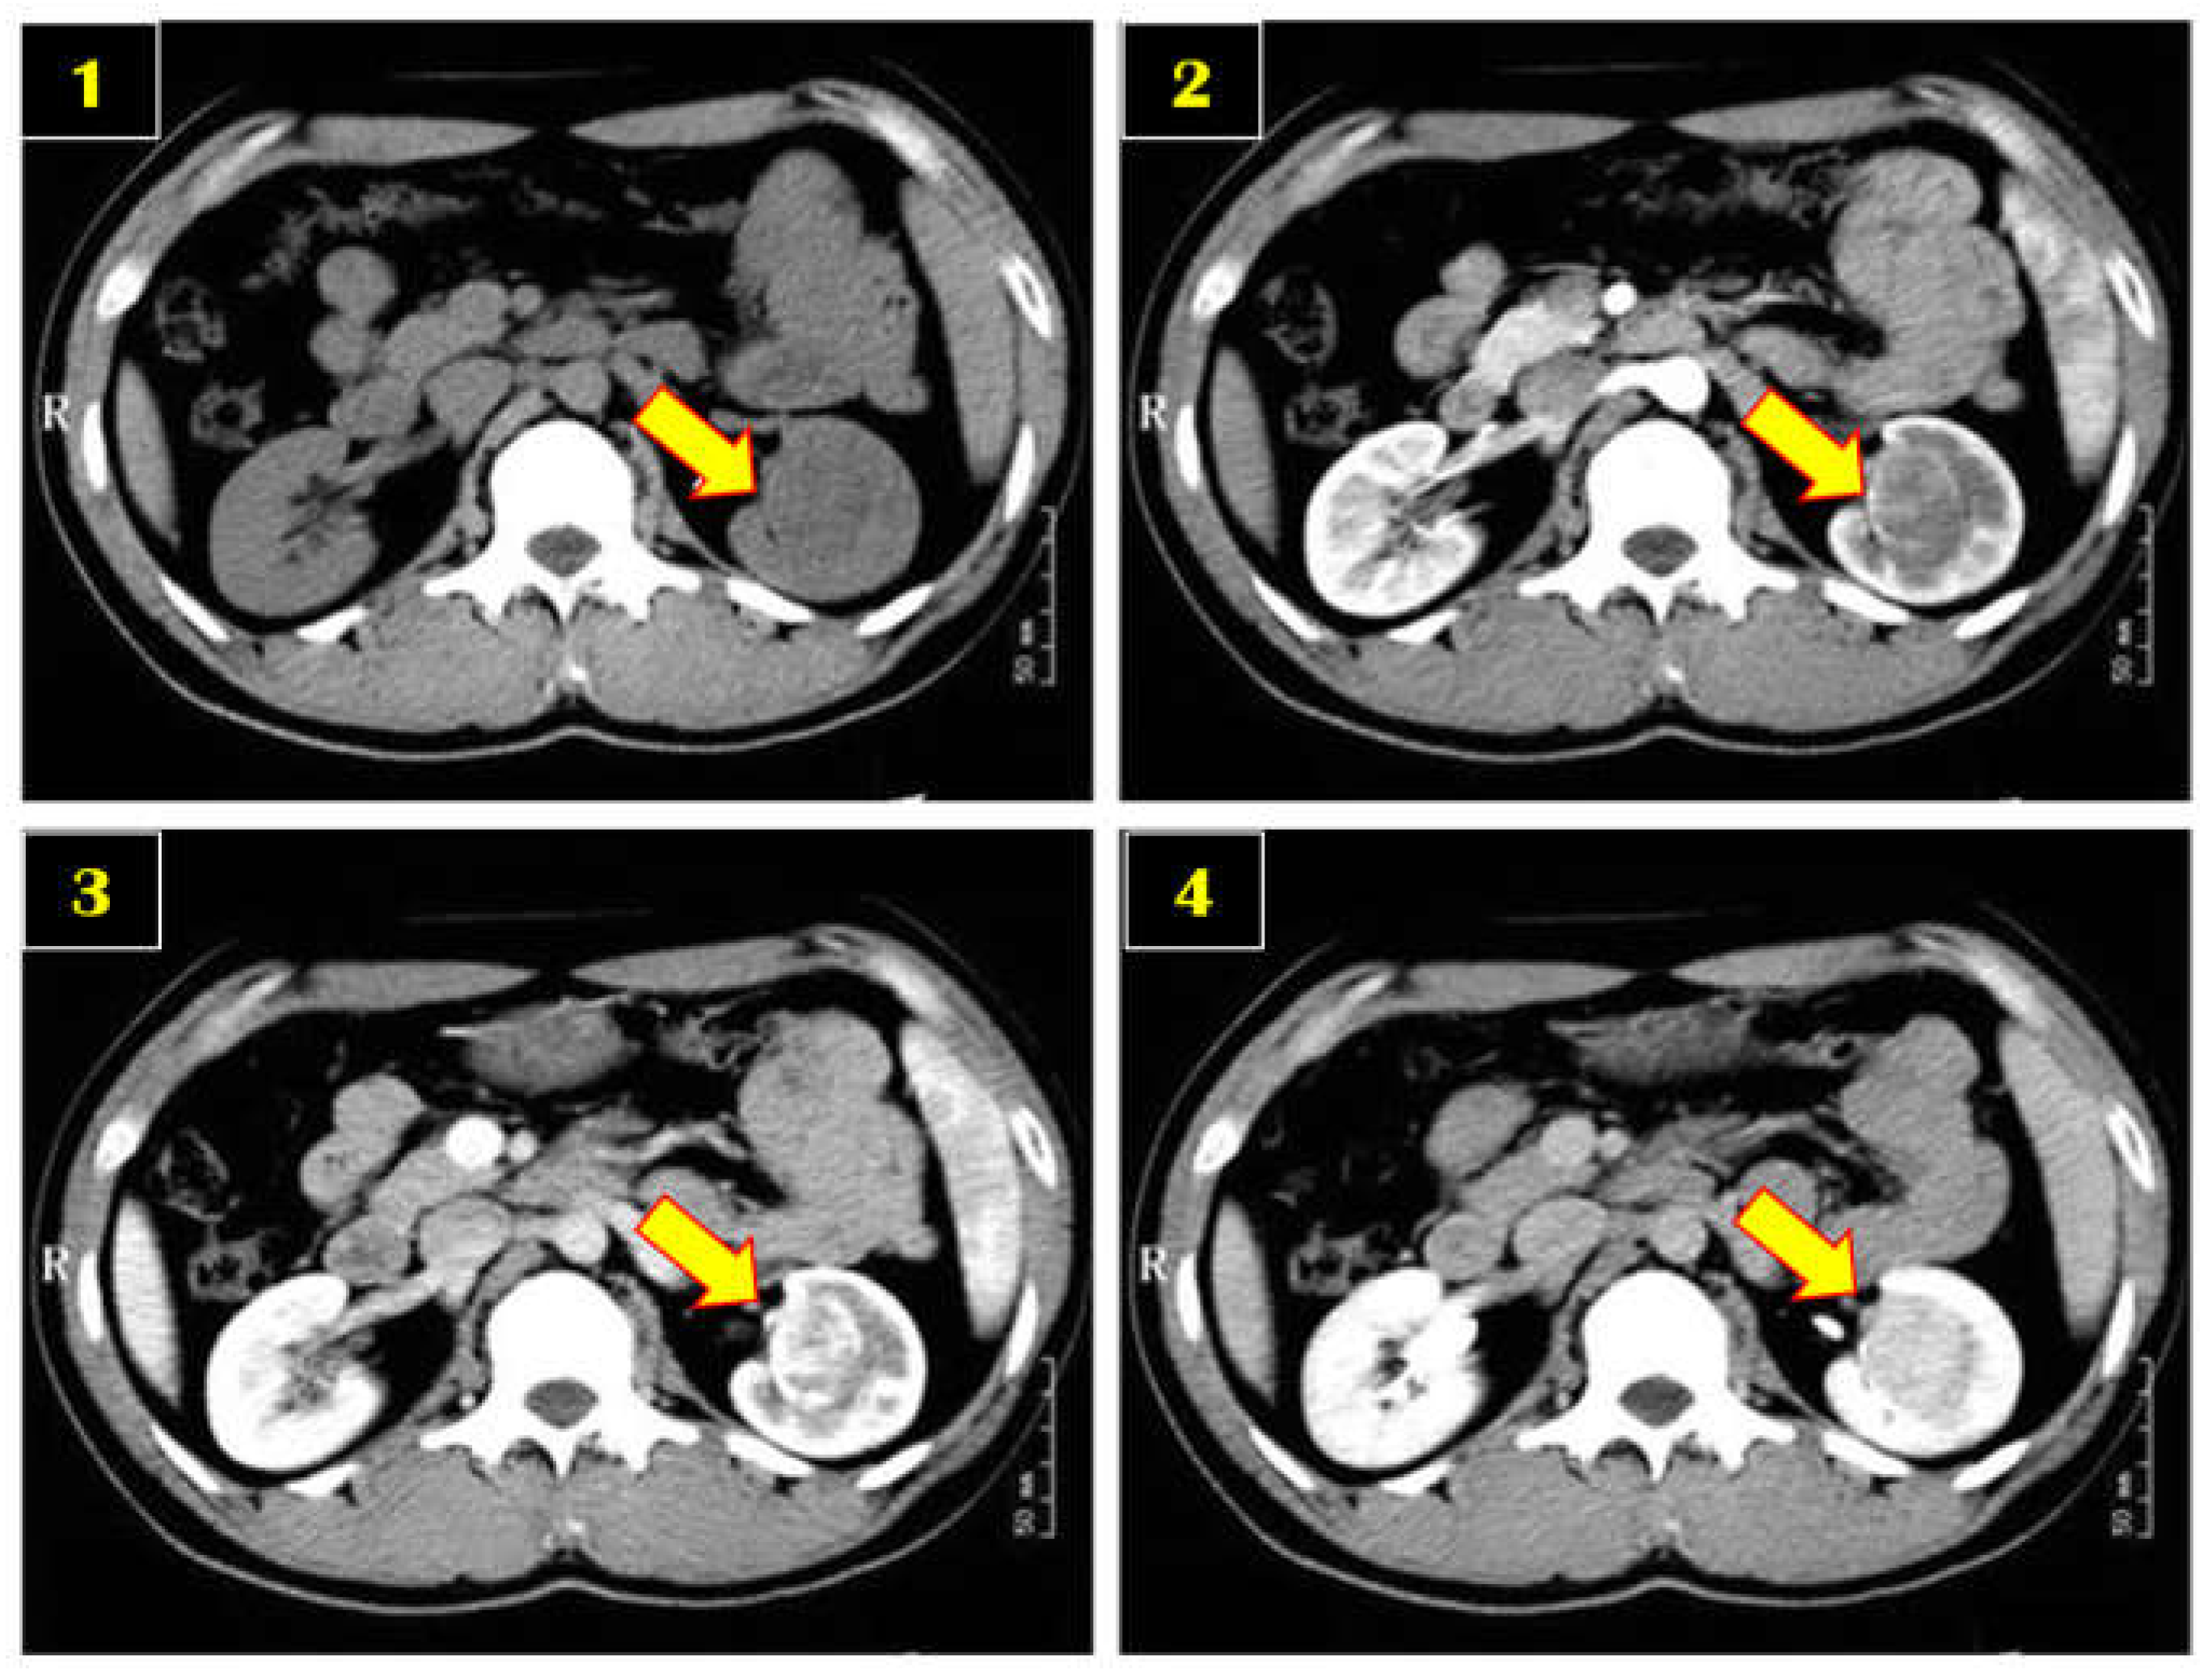

3.2. Contrast-Enhanced Computed Tomography

5.1. HCC Type of Liver Cancer